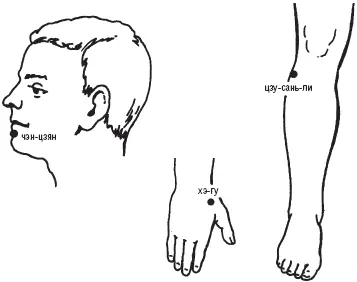

Владимир Васичкин - Лечебные точки организма - снимаем боли в сердце и в области живота

- Название:Лечебные точки организма: снимаем боли в сердце и в области живота

Лечебные точки организма: снимаем боли в сердце и в области живота: краткое содержание, описание и аннотация